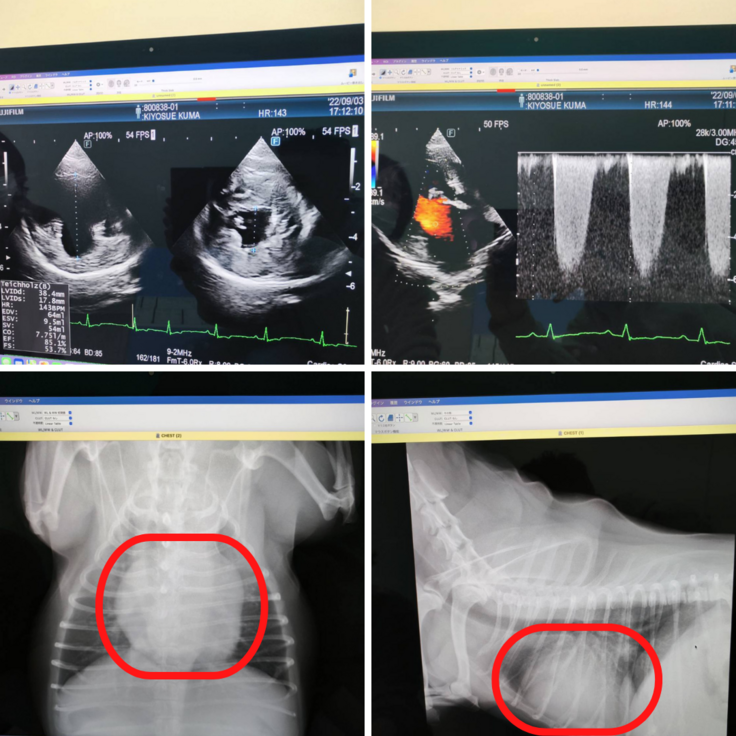

最初は遊び疲れただけかな?と思っていましたが、それ以来苦しそうに咳き込んでしまう日々が続いたため病院で受診したところ、2020年8月下旬に心臓に雑音があると診断され、それからは薬での治療を始めました。しかし一向に容体は良くならないため、心臓病専門の大きな病院で検査を受けた結果、2022年9月3日に「僧帽弁閉鎖不全症ステージB2とCの間」と診断を受けてしまいました。